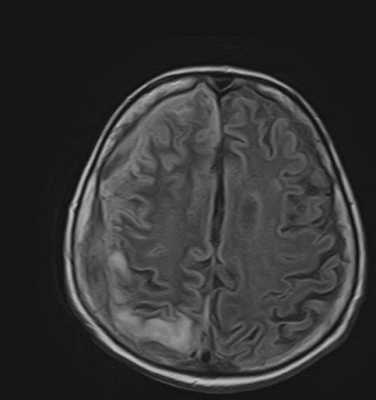

Первоначальные признаки патологии - неврологические расстройства. Неврологи проводят дифференциальную диагностику, позволяющую заподозрить менингоэнцефалит, своевременно назначить методы нейровизуализации (МРТ головного мозга и КТ).

МРТ менингоэнцефалит

Клинико-инструментальные методы обследования церебральной паренхимы - рентгенография, КТ, МРТ, электроэнцефалография (ЭЭГ). Нейровизуализация определяет распространение воспаления, глубину поражения, сопутствующую патологию.